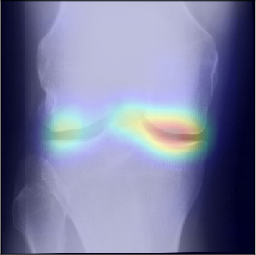

To gain insight into the basis of the CNN’s prediction, we used the GradCAM [24] approach and visualized the attention maps for the well-predicted knees. Examples of attention maps are presented in Figure 5. We observed that in various cases, the CNN paid attention to the compartment opposite to the one where degenerative change became visible during the follow-up visits. Additional examples of such attention maps are presented in Supplementary Figures 3, 4, 5 and 6.

Refer to caption

(a)

(b)

(c)

(d)

Figure 5: Examples of attention maps for progression cases and the corresponding visualization of progression derived using follow-up images from MOST datasets. Here, subplots (a) and (c) show the attention maps derived using a GradCAM approach. Subplots (b) and (d) show the joint-space areas from all the follow-up images (baseline to 84 months). Here, the subplot (b) corresponds to the attention map a) and the subplot (d) corresponds to the attention map (c).